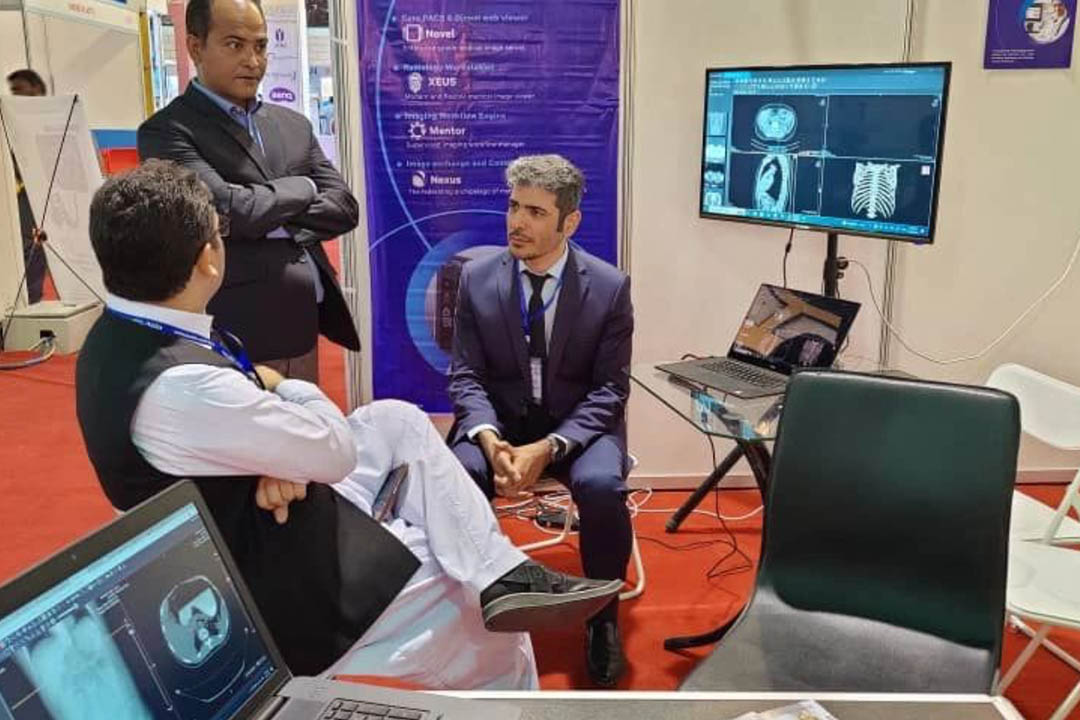

Medical imaging is entering a new era—where speed, mobility, and intelligent workflows matter more than ever. Traditional PACS and workstation-bound viewers, once considered state-of-the-art, now